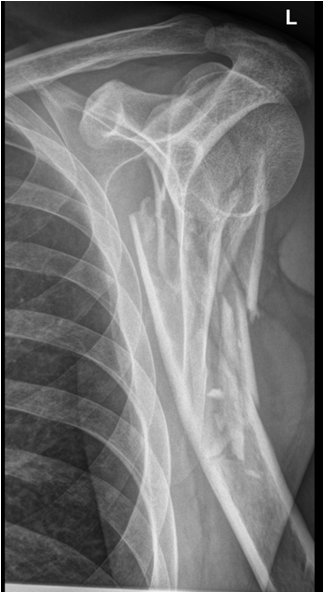

Fig. 12. A) Complete dislocation with contraction in the elbow joint. Ulna and radius are both dislocated and dorsally displaced. B.) Anterior and inferior dislocation of the humerus.